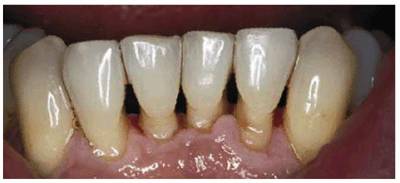

procedure can be seen in Figures 17-8A

and B 17-8C 17-8D 17-8E 17-8F 17-8G 17-8H and I, which show a 45-year-old man with

evidence of gingival and incisal abrasion, erosion, and abfraction. It is

Figure 17-8A and B: This 45-year-old man shows extreme tooth loss due to combination lesions both gingivally and incisally of abrasion, erosion, and abfraction.

Figure 17-8D: Note how clean the teeth appear after a thorough prophylaxis with an air polisher.